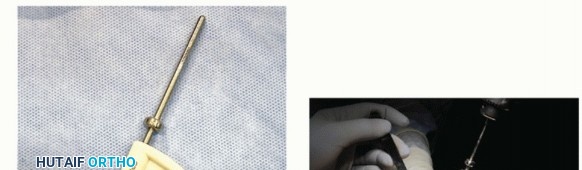

A circular surface reamer is then used (TECH FIG 4). The proper size is the largest size measured in either the superoinferior or mediolateral dimensions. For example, if superoinferior measures 4.5 mm and mediolateral 2.5 mm, then use a 4.5-mm circular reamer. Note: It is important to start the reamer before contacting the bone to avoid the remote chance of uncontrolled metatarsal bone blowout if poor bone quality is noted. The depth of the reamer is controlled, for it will stop on its own when contacting the screw.

- TECH FIG 4 • A. A circular reamer is used over the guide pin. B. Start reamer prior to bone contact. There is a built-in stop when it reaches the edge of the screw. C. View after reaming for bone preparation for the HemiCAP. The screw is seen within the metatarsal head, for which the cap will mate with the Morse taper interlock.